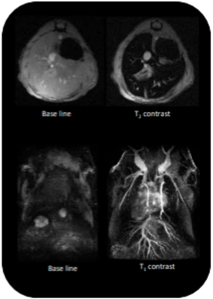

Imagen de hígado ponderada en T1: basal (izda) y después de administrar nanopartículas de hierro con un tamaño relativamente grande (dcha.) Se observa una hipointensidad en la señal. Angiografía en T1: antes de administrar el contraste (izda) y después de administrar nanopartículas de hierro con un tamaño muy inferior a las anteriores. Se produce una hiperintensidad en la señal.

Imagen multimodal RM-SPECT. Al animal se le administró un compuesto dual marcado con Tecnecio y con partículas de óxido de Hierro. Para la imagen de RM se tomó la imagen en basal y después se fueron adquiriendo imágenes cada x minutos para ver el aumento de la señal tanto en los vasos como en el corazón. Para adquirir la imagen SPECT es necesario esperar un tiempo denominado captación. Las imágenes se obtuvieron a los 40 y 200 min. después de la inyección del compuesto.